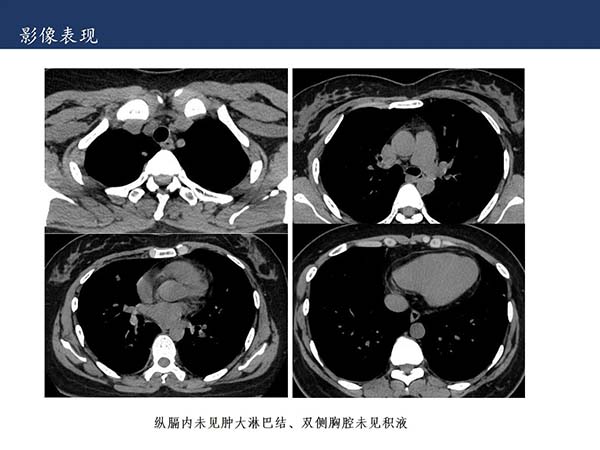

【杨柳科普】肺上皮样血管内皮瘤的影像表现